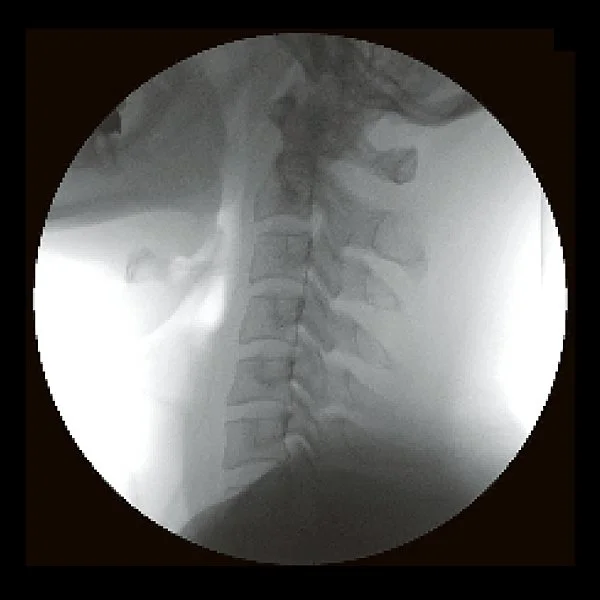

Take 2. Neck (C-spine) without RadSafe Filter

Take 2. Neck (C-spine) with RadSafe Filter